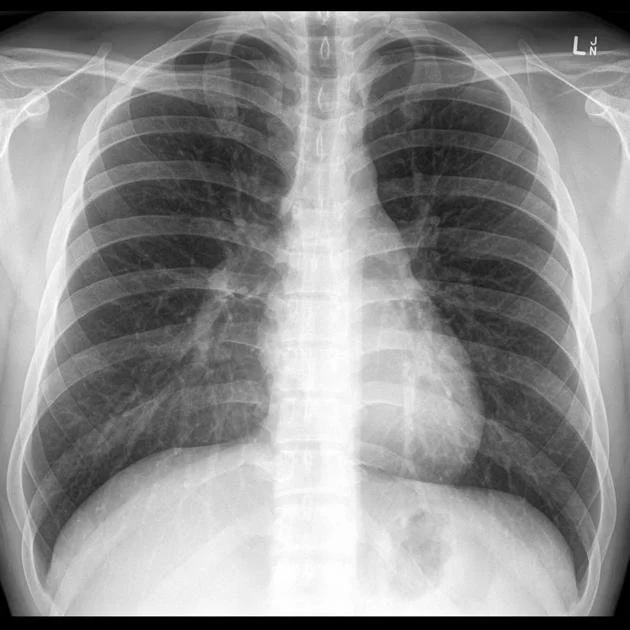

Review your medical imaging results one-on-one with a radiologist including pertinent findings in the report, their correlation on imaging and potential clinical impact